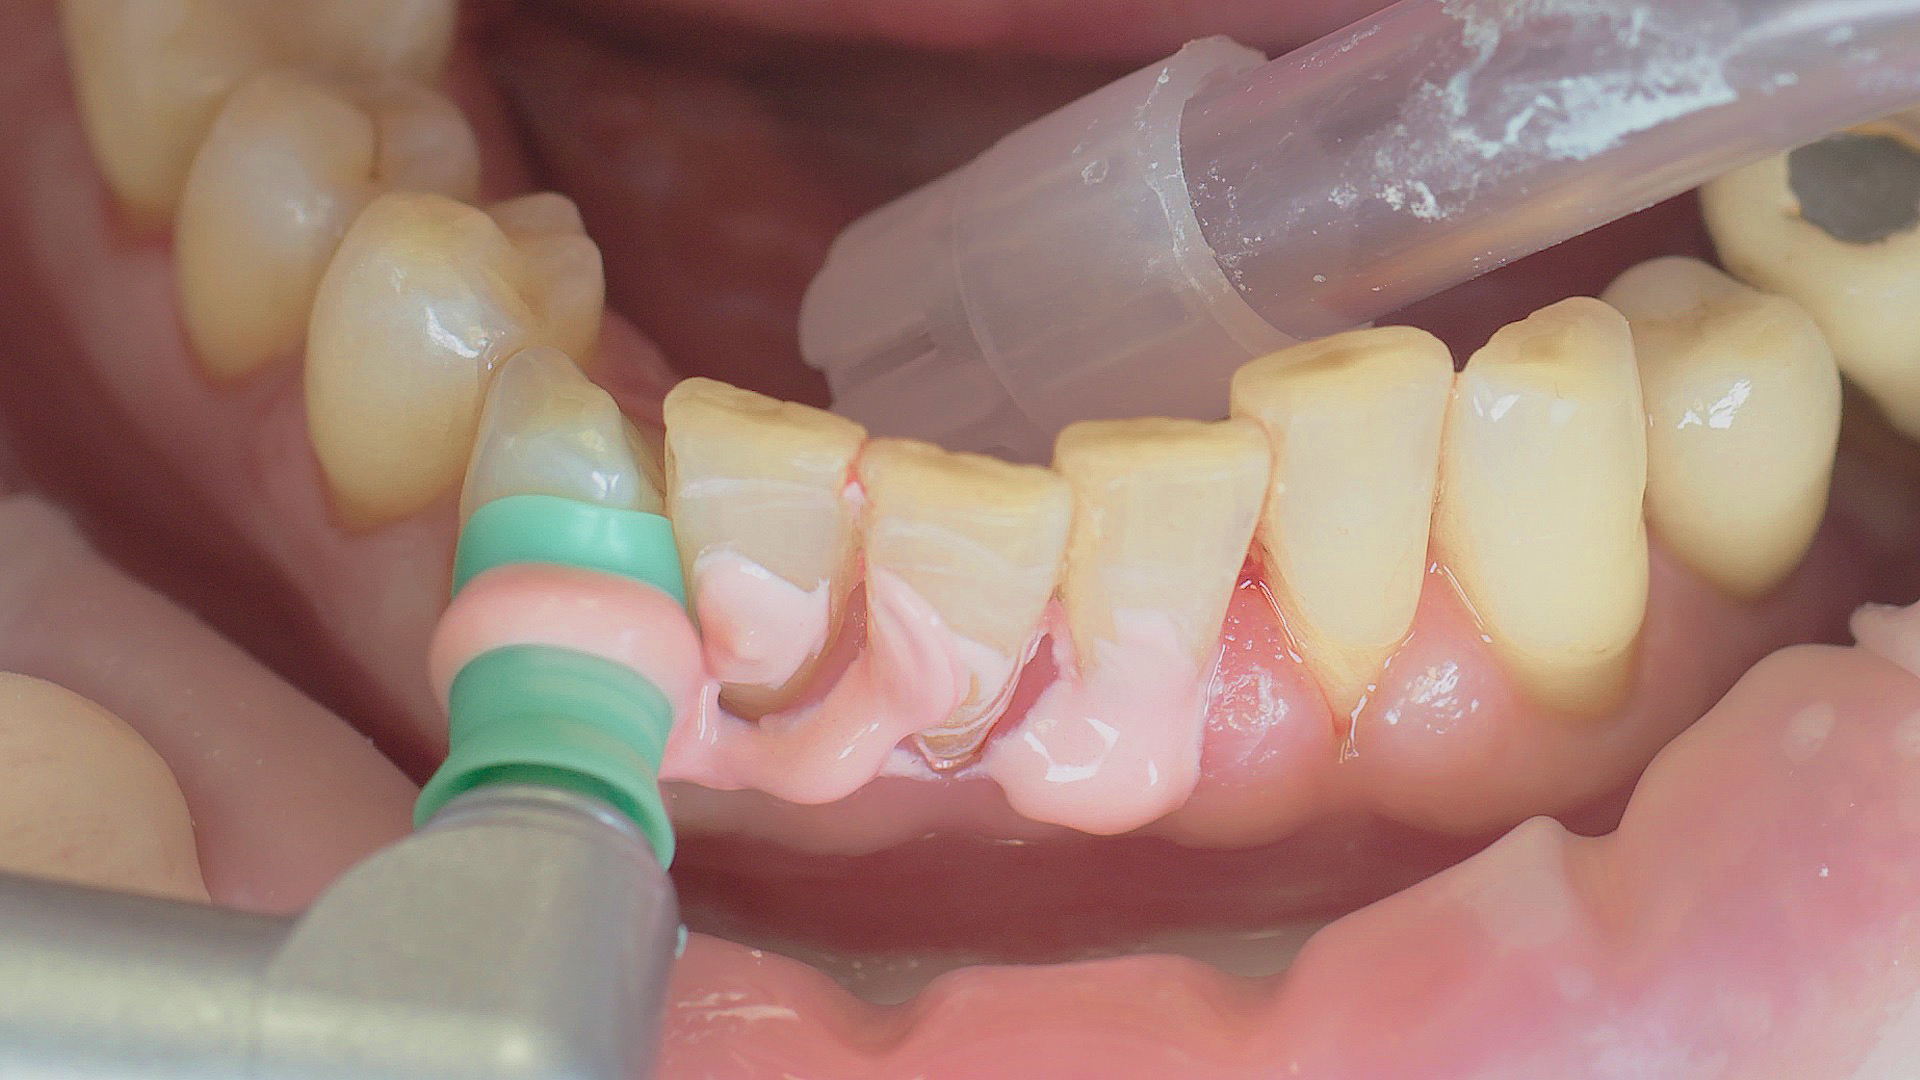

In the periodontal aftercare subsequent to implantation, soft (biofilm) and hard coatings are regularly professionally and mechanically removed.[16, 17] In the subgingival and supragingival areas, ultrasonic devices are generally used for this (Fig. 4), in combination with manual instruments where necessary. Alternatively, subgingival air polishing can be used in combination with periodontal attachments and powders.[18]